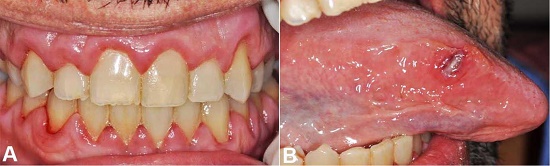

A 48-year male patient sought the emergency department complaining of malaise, sore throat, earache, and fever over the last week. His past medical history was unremarkable. The oral examination revealed generalized swollen gingiva on the buccal and lingual surfaces and petechiae (Figure 1A). The finding resembled hyperplasia and presented with spontaneous bleeding. On the right lateral border of the tongue, there was a hardened and ulcerated lesion of approximately 0.5cm (Figure 1B).

The cytogenetic analysis revealed a normal karyotype, and the panel of myeloid mutations by next-generation sequencing revealed mutations in FLT3, NPM1, and DNMT3 genes confirming the diagnosis of acute myeloid leukemia (AML). Daunorubicin (90 mg/m2) and cytarabine were given as induction chemotherapy. The patient had complete involution of the oral manifestations (gingival enlargement and the tongue ulcer) after 15 days of the first cycle of chemotherapy (Figure 4A and Figure 4B).